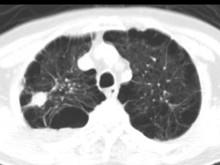

问题 男,76岁,气喘数年,胸痛一月余,结合影像图像,选择最可能的诊断 ( )

选项 A、右上肺错构瘤 B、右上肺肉瘤 C、肺间质纤维化 D、右上肺瘢痕癌 E、右上肺结核球

答案 D